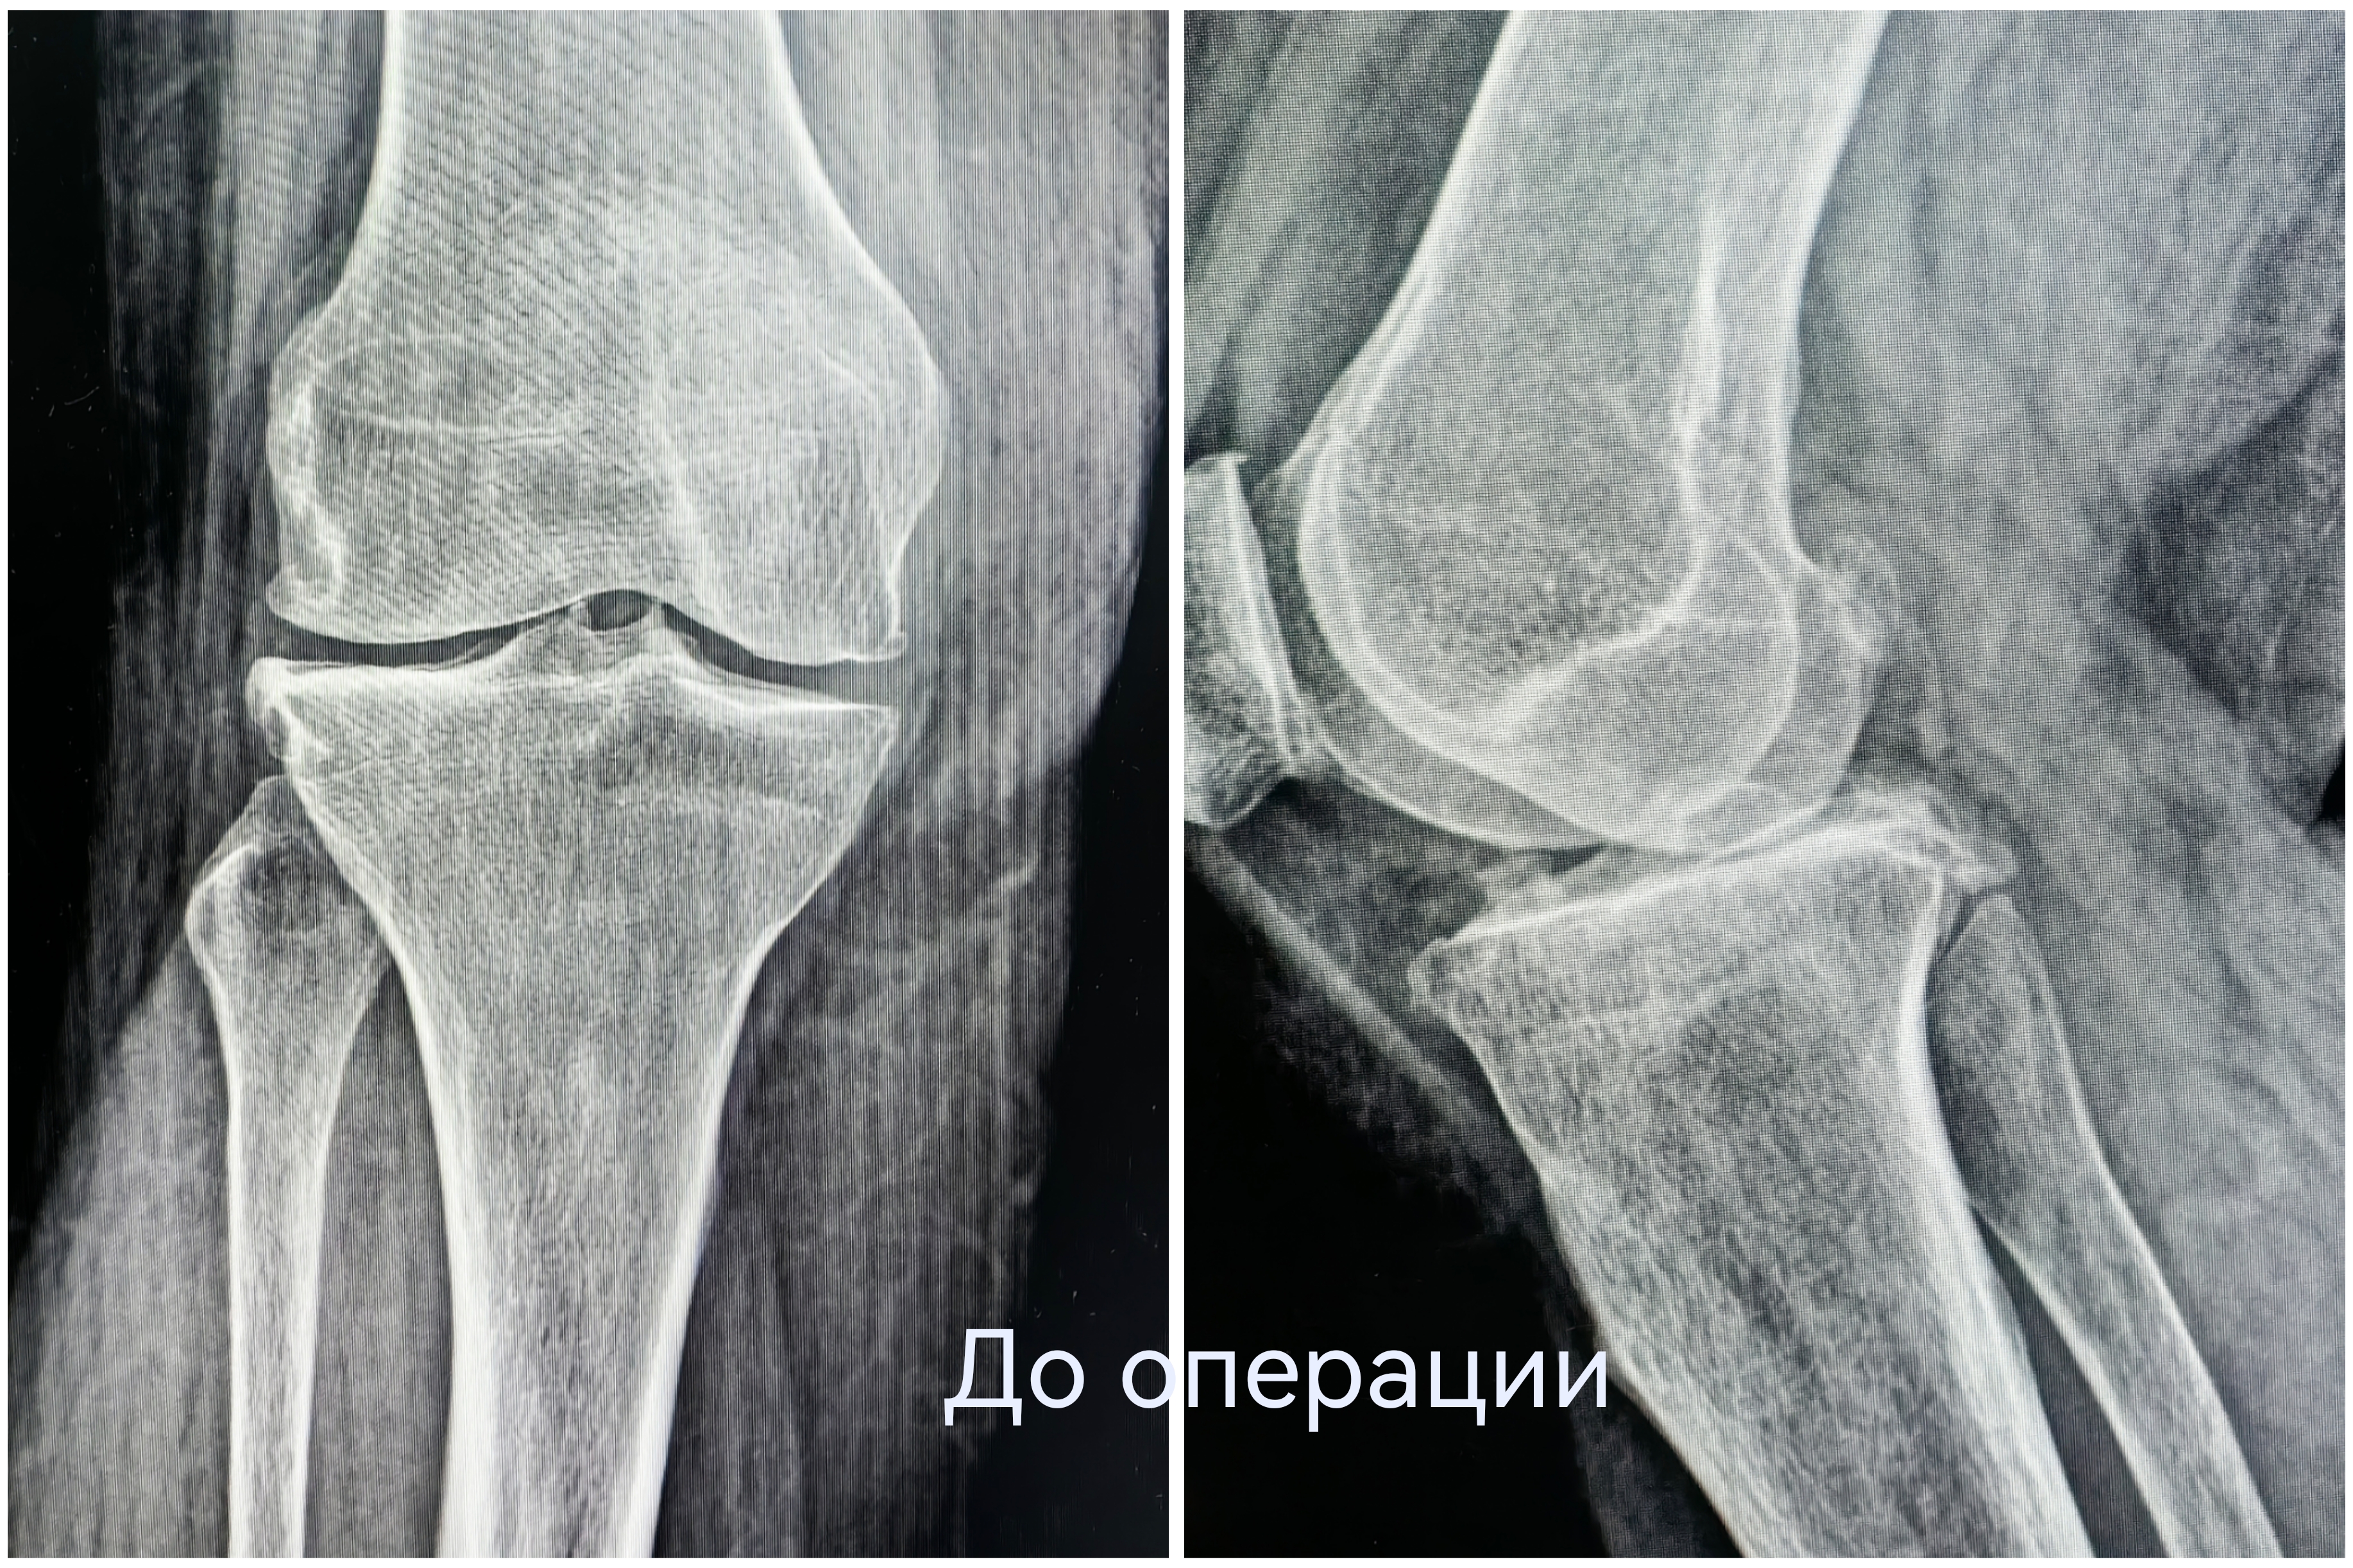

Чтобы избавиться от мучительной боли в колене, наша 55-летняя пациентка готова была избавиться от всего сустава. При госпитализации женщина настроилась на эндопротезирование. Однако травматологи-ортопеды выбрали другую тактику. При вальгусной деформации и деформирующем артрозе второй стадии коленный сустав оставался достаточно сохранным. Чтобы спасти его от замещения металлоконструкцией, была выполнена корригирующая остеотомия.

Суть операции – в исправлении нарушенной оси конечности. После перестроения и выравнивания костей голени нагрузка собственного веса смещается с пораженной части сустава на здоровую. Таким образом, болевой синдром регрессирует, а износ сустава замедляется.

Технически корригирующая остеотомия не представляет сложности. Непосредственно в операционной для опытного хирурга работы - на полчаса. А вот предварительное планирование – это целое исследование с множеством математических измерений и расчетов. В профессиональной среде говорят, что такая операция делается в основном в ординаторской. И это действительно так. До хирургического вмешательства врач должен предельно точно определить ось конечности, градус её отклонения и угол коррекции.

В случае с этой пациенткой ради сохранения коленного сустава пришлось пожертвовать 10 миллиметрами большеберцовой кости. Костный клин такого размера был удалён, чтобы вернуть конечность в правильную механическую ось. Небольшие размеры современных фиксаторов позволяют выполнять операции малотравматичным доступом – через 4-5-сантиметровый разрез.